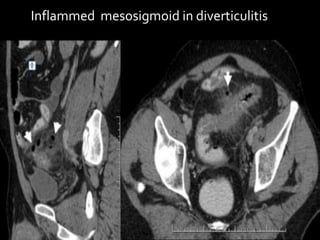

Inflammed mesosigmoid in diverticulitis

Mesenteries

True mesenteries all connect to the

posterior peritoneal wall.

These are:

The small bowel mesentery

The transverse mesocolon

The sigmoid mesentery (or

mesosigmoid)

Mesenteries True mesenteries allconnect to the posterior peritoneal wall. These are: The small bowel mesentery The transverse mesocolon The sigmoid mesentery (or mesosigmoid) Specialized mesenteries do not connect to the posterior peritoneal wall. These are: The greater omentum: connects the stomach to the colon The lesser omentum: connects the stomach to the liver The mesoappendix: connects the appendix to the ileum